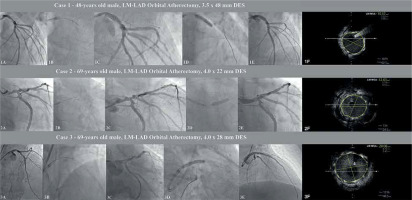

Figure 1

Selected procedures of OA-LM-PCI: 1A – initial LM lesion, 1B – orbital atherectomy (OA) burr passage, 1C – post-OA control angiogram, 1D – DES implantation, 1E – final post-PCI angiogram, 1F – final IVUS assessment, 2A – initial LM lesion, 2B – orbital atherectomy (OA) burr passage, 2C – post-OA control angiogram, 2D – DES implantation, 2E – final post-PCI angiogram, 2F – final IVUS assessment, 3A – initial LM lesion, 3B – orbital atherectomy (OA) burr passage, 3C – post-OA control angiogram, 3D – DES implantation, 3E – final post-PCI angiogram, 3F – final IVUS assessment